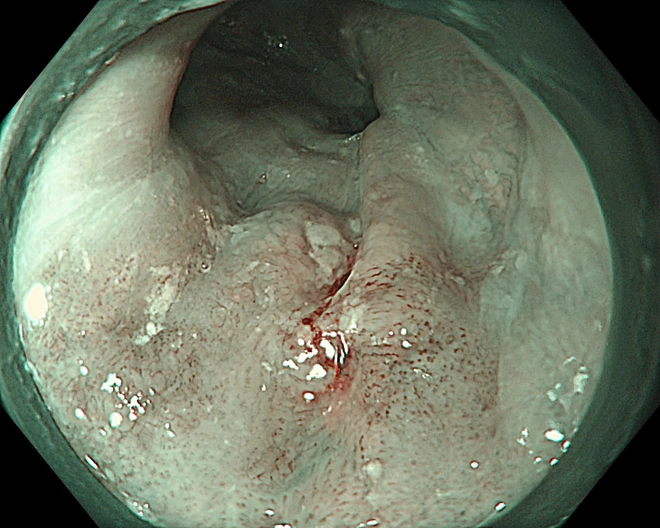

Hình ảnh tổn thương thực quản của bệnh nhân.

Trong một trường hợp khác, bệnh nhân 67 tuổi được phát hiện tổn thương qua nội soi công nghệ cao. Tuy nhiên, qua đánh giá chuyên sâu, bác sĩ xác định tổn thương đã vượt chỉ định điều trị nội soi và chuyển sang phẫu thuật.

Kết quả mô bệnh học sau đó xác nhận ung thư đã xâm lấn dưới niêm mạc, phù hợp với chỉ định ngoại khoa.

Thực tế này cho thấy vai trò quan trọng của nội soi công nghệ cao kết hợp với kinh nghiệm lâm sàng trong việc đánh giá chính xác giai đoạn bệnh, từ đó đưa ra phương pháp điều trị phù hợp, tối ưu.